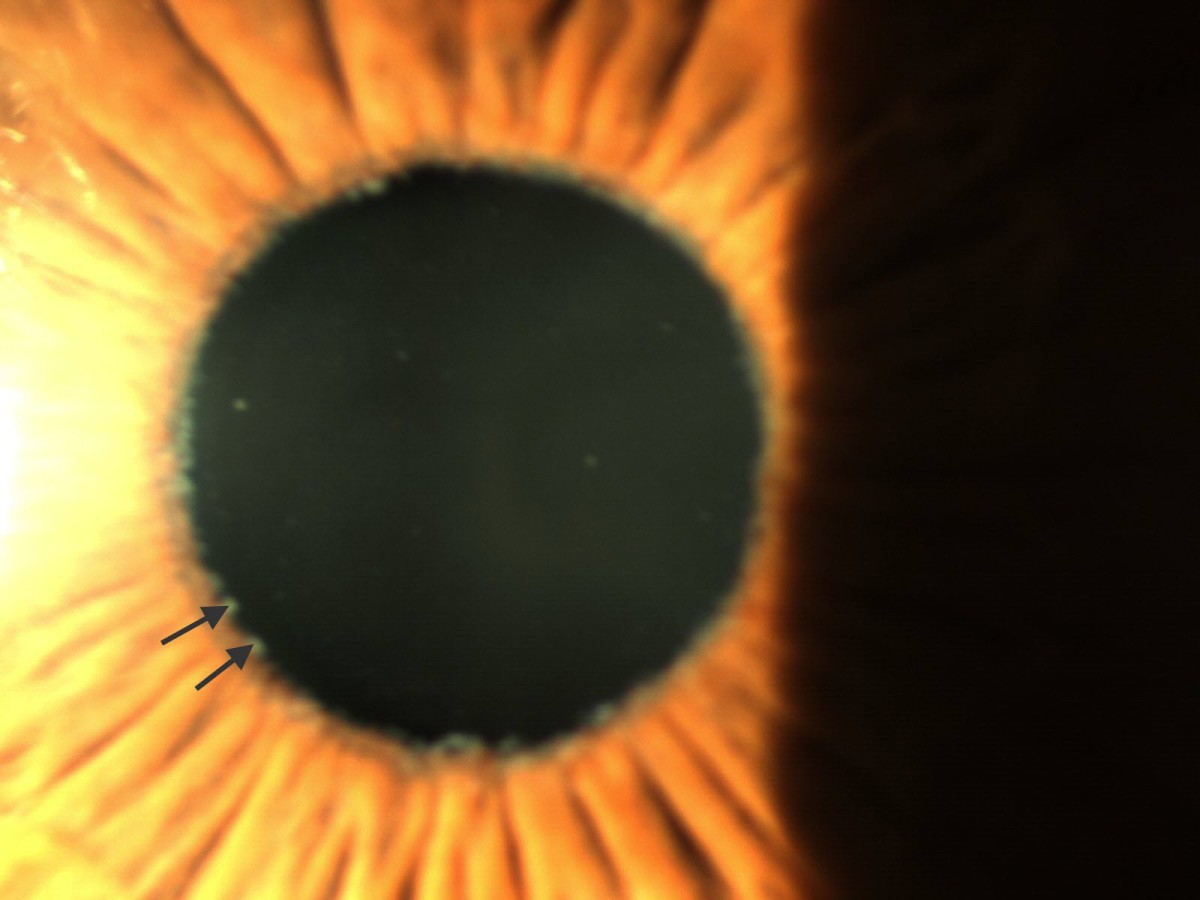

A 74yearold woman with pseudoexfoliation of the anterior lens surface Lens Pseudoexfoliation Pseudoexfoliation syndrome is a condition that is caused by tiny flakes that build up in the front of the eye. Review the risk factors for developing pseudoexfoliation syndrome (pex) and pseudoexfoliation glaucoma (peg). These clumps, that look like dandruff flakes, can clog the eye’s drainage area and raise eye pressure, eventually leading to glaucoma, cataracts and possible vision loss. Here,. Lens Pseudoexfoliation.